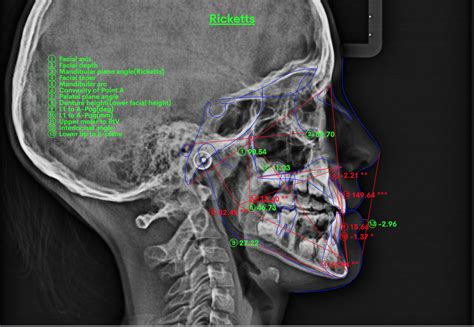

Estos hallazgos clínicos pueden conducir al clínico al diagnostico de EMV, lo que debe confirmarse con una cefalometría. En un grupo que presentaba sonrisa gingival se encontró que la distancia entre el plano palatino y el borde incisal de los incisivos superiores (altura facial anterior) era aproximadamente 2 mm más alta que la de individuos que no presentaban sonrisa gingival.